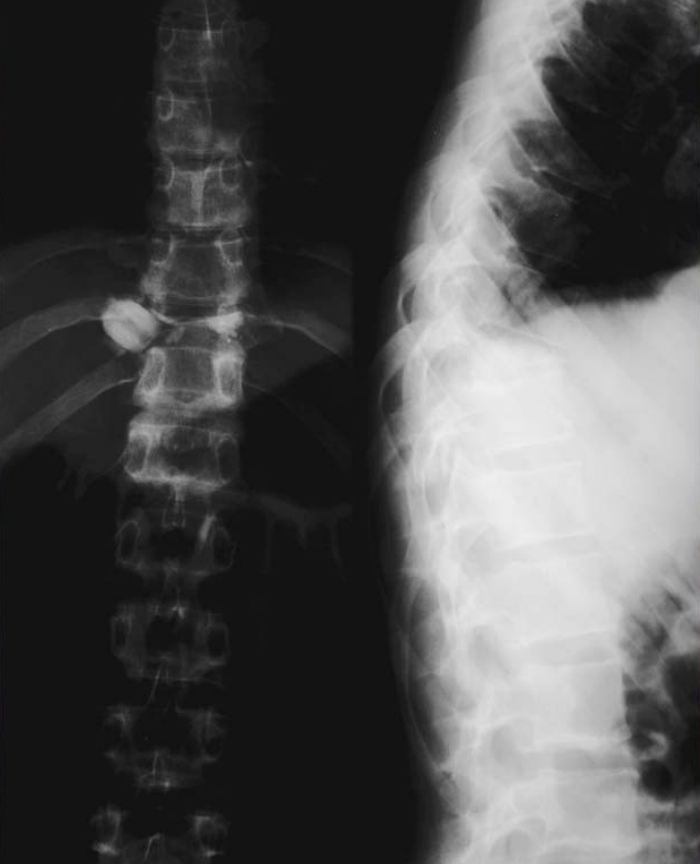

Figure3